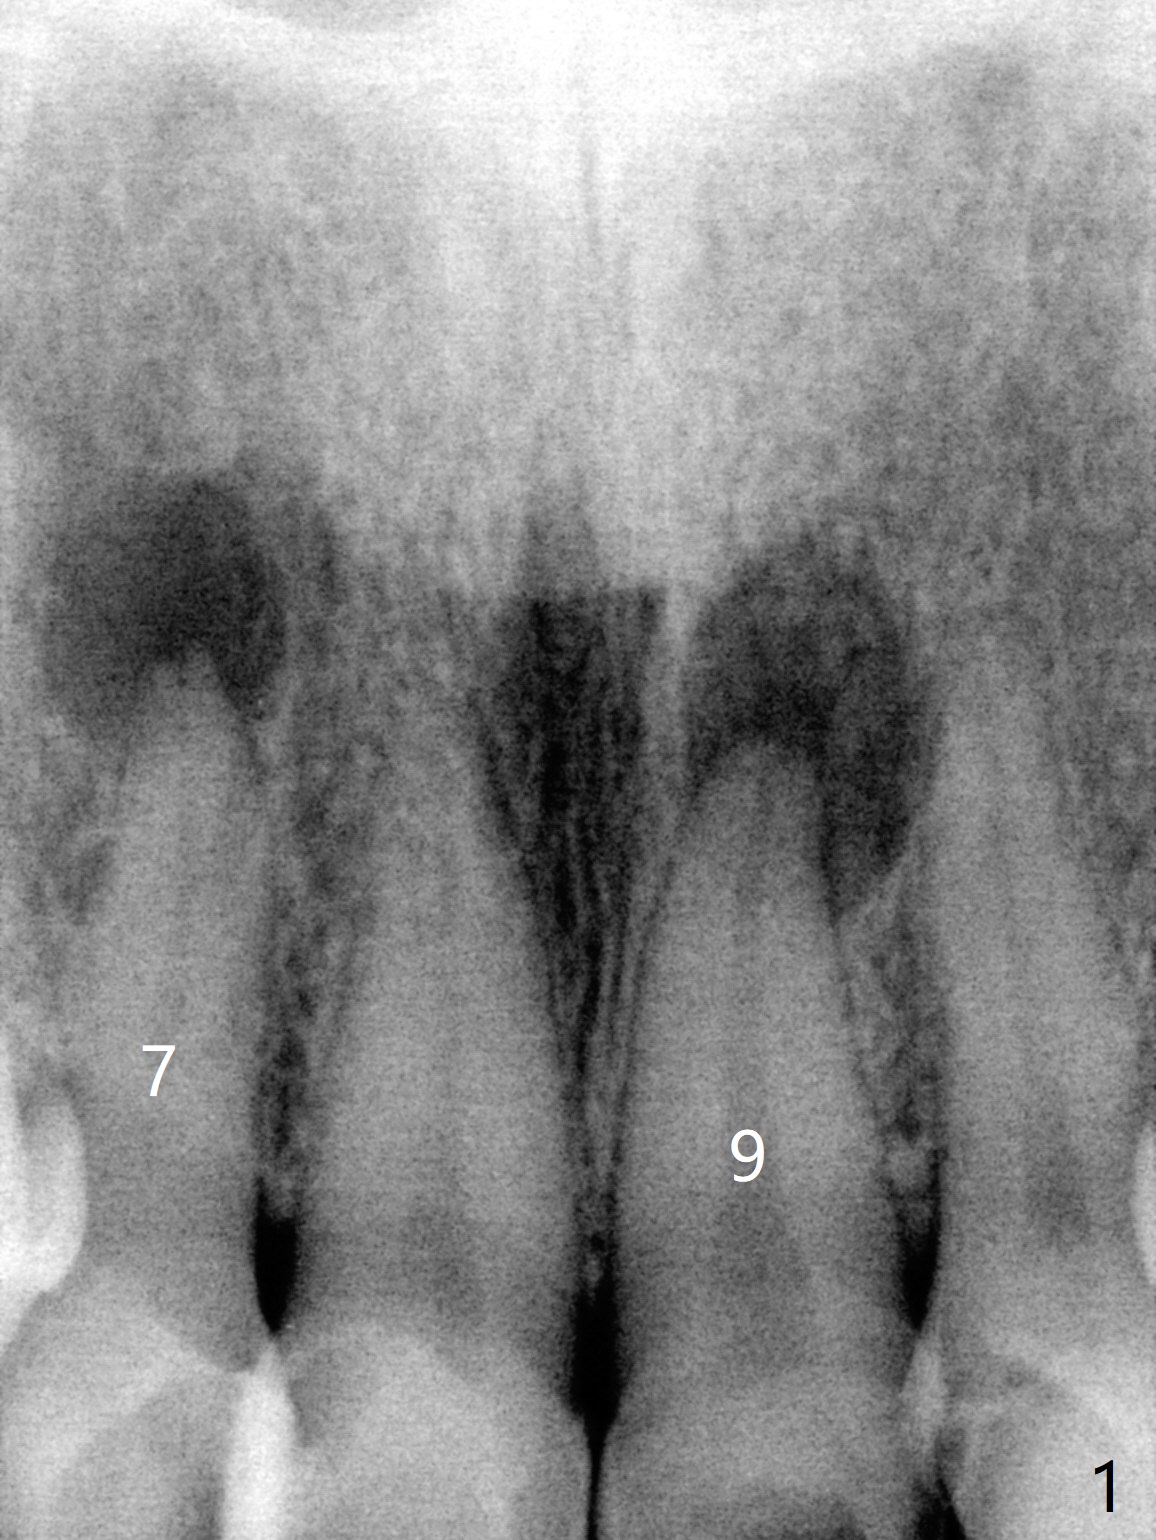

A 47-year-old woman (dental phobic) presented to clinic 9.5 years ago with periapical radiolucency (PARL) at #7 and 9 (Fig.1). RCT was done at #9 because of fistula and symptom 6 months later (Fig.2). While PARL increases at #7 without symptom, that at #9 disappears 8.5 years postop. Three months later, the patient returns for #7 RCT because of the abscesses (Fig.4 *) and pain. Intraop PA is taken with a 30/.06 rotary file in the canal with 19 mm working length (Fig.5). After use of #15 hand file for 20 mm, Ca(OH)2 paste is applied in the canal. When the rubber dam is removed, the abscesses enlarge (Fig.6), which may be related to sodium hypochlorite leakage. A dental explorer is used to try to find a bony opening to the large PARL without success (Fig.7). A postop PA reveals the leakage of Ca(OH)2 paste (Fig.8). Review of the preop PA (Fig.3,9) and intraop PAs (Fig.5,10) shows possible apical resorption and open apical foramen, which is the basis for the paste leakage (Fig.8,11). Careful analysis (with magnification and room light off) of pre- and intra-op PAs should be able to avoid use of #15 hand file out of apical constriction and the complication. The abscess has receded 1 month later (Fig.12). The paste has been resorbed 1 month later (Fig.13). A 30/.06 Gutta Percha is inserted at 18.5 mm (Fig.14 vs. 30/.06 file at 19 mm, 15 file at 20 mm last visit). Fig.15 is the final PA after closure of the access with composite (Fig.15).